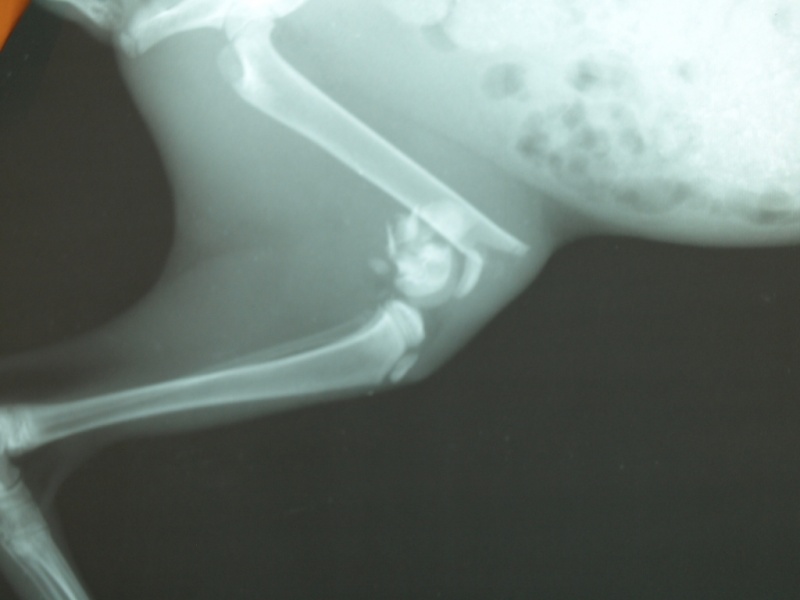

Нужно выложить рентген и лист назначений. По деньгам нужно будет делать отчет.

Проблем, конечно нет, только это время которого нет (( Боюсь, что у нее уже начали кости срастаться.Вам же, наверное, все равно надо будет в клинику идти, договариваться об операции, назначать дату? Это нужно сделать как можно скорее, у врачей тоже свое расписание.

тема о пристроее создана больше месяца назад.Что произошло с котенком я не знаю. Подобрала уже со сломанной лапкойи

Боюсь, что у нее уже начали кости срастатьсяПолучается котёнок месяц с переломом мучался((.